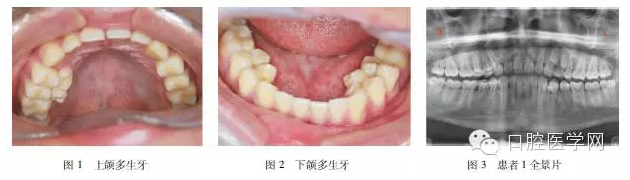

患者1,男,16歲,患者2年余前發(fā)現(xiàn)口內(nèi)長(zhǎng)出多顆多余牙齒。奶奶及父親均有多余牙拔除史,具體不詳,母親孕期無特殊接觸史。??茩z查:恒牙32顆完全萌出,545445舌側(cè)及34之間舌側(cè)各可見1顆多生牙,5舌側(cè)多生牙可見冠部齲損(上頜多生牙見圖1,下頜見圖2)。全景片(圖3)示患者前磨牙區(qū)多生牙共9顆,其中萌出7顆,左上頜2顆埋伏阻生,位于恒牙根旁。

治療計(jì)劃:分次拔除7顆多生牙,2顆埋伏多生牙因無臨床癥狀,可暫觀察。拔除的多生牙牙根均發(fā)育完全,形態(tài)除34之間1顆似下尖牙,其余均似前磨牙,牙體比正常牙略小。圖4所示是拔除的左下頜3顆多生牙。